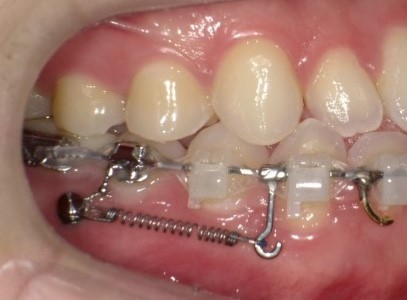

판교교정치과 교정치료에서 가장 많이 쓰이는 스프링 3종 분석 | 서울리인치과교정과